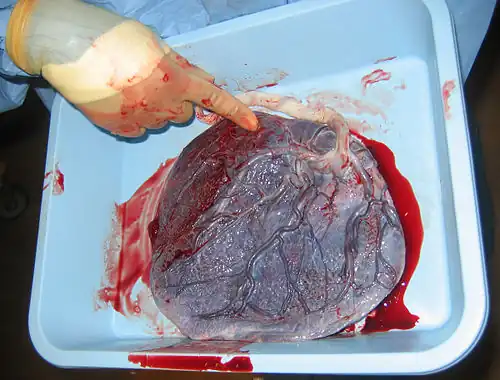

The third stage of labor is the delivery of the afterbirth (placenta).

Oxytocin continues to be released to shrink the size of the uterus and aid in the limiting of blood loss from the site of the placenta. As the uterus shrinks the attachment site blood vessels, some of which can be as large as an adult finger, shrink also. The average blood loss in a routine vaginal delivery is 400-500 cc.

- Placental Abruption is a condition in which the placenta is torn away from the uterine wall causing loss of oxygen and nutrients to the baby, and hemorrhage of mother and baby from the large blood vessels in the placenta. Most women, but not all experience heavy bleeding and abdominal pain. This is a life threatening emergency as a fetus can only survive as long as 50% of the placenta is still attached.

Abruption: Premature separation of the placenta from the wall of the womb

Placenta: The structure by which an unborn child is attached to it's mother's uterine wall and through which it is nourished.